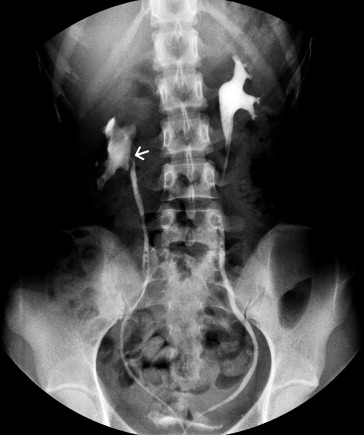

Renal Doppler ultrasound was performed, and peak velocity (PV) was measured at the hilar and aortomesenteric portions of the LRV. In the upright position, the PV in the hilar and aortomesenteric portion of the LRV were 28.4 and 200 cm/s, respectively, and the PV ratio was 7.04; the anteroposterior diameters were 11.1 mm and 1.3 mm (Fig. 1), respectively, and the ratio of the AP diameters was 8.6. The pressure gradient between LRV and inferior vena cava was 16 mmHg. It also showed dilatation of the right renal pelvis. Magnetic resonance angiography (MRA) showed that the LRV is compressed between the AO and the SMA, and the hilar portion of the LRV was distended (Fig. 2). The SMA delineated sharply from the AO, and the aortomesenteric angle where the LRV crosses was 15°. Retrograde pyelograthy (Fig. 3) and magnetic resonance urography revealed right-sided ureteropelvic junction stenosis and hydronephrosis. From these findings, a diagnosis of left nutcracker syndrome and right UPJO was made.

Retrograde pyelography showing right-sided hydronephrosis and ureteropelvic ...

Retrograde pyelography showing right-sided hydronephrosis and ureteropelvic junction stenosis (arrow).